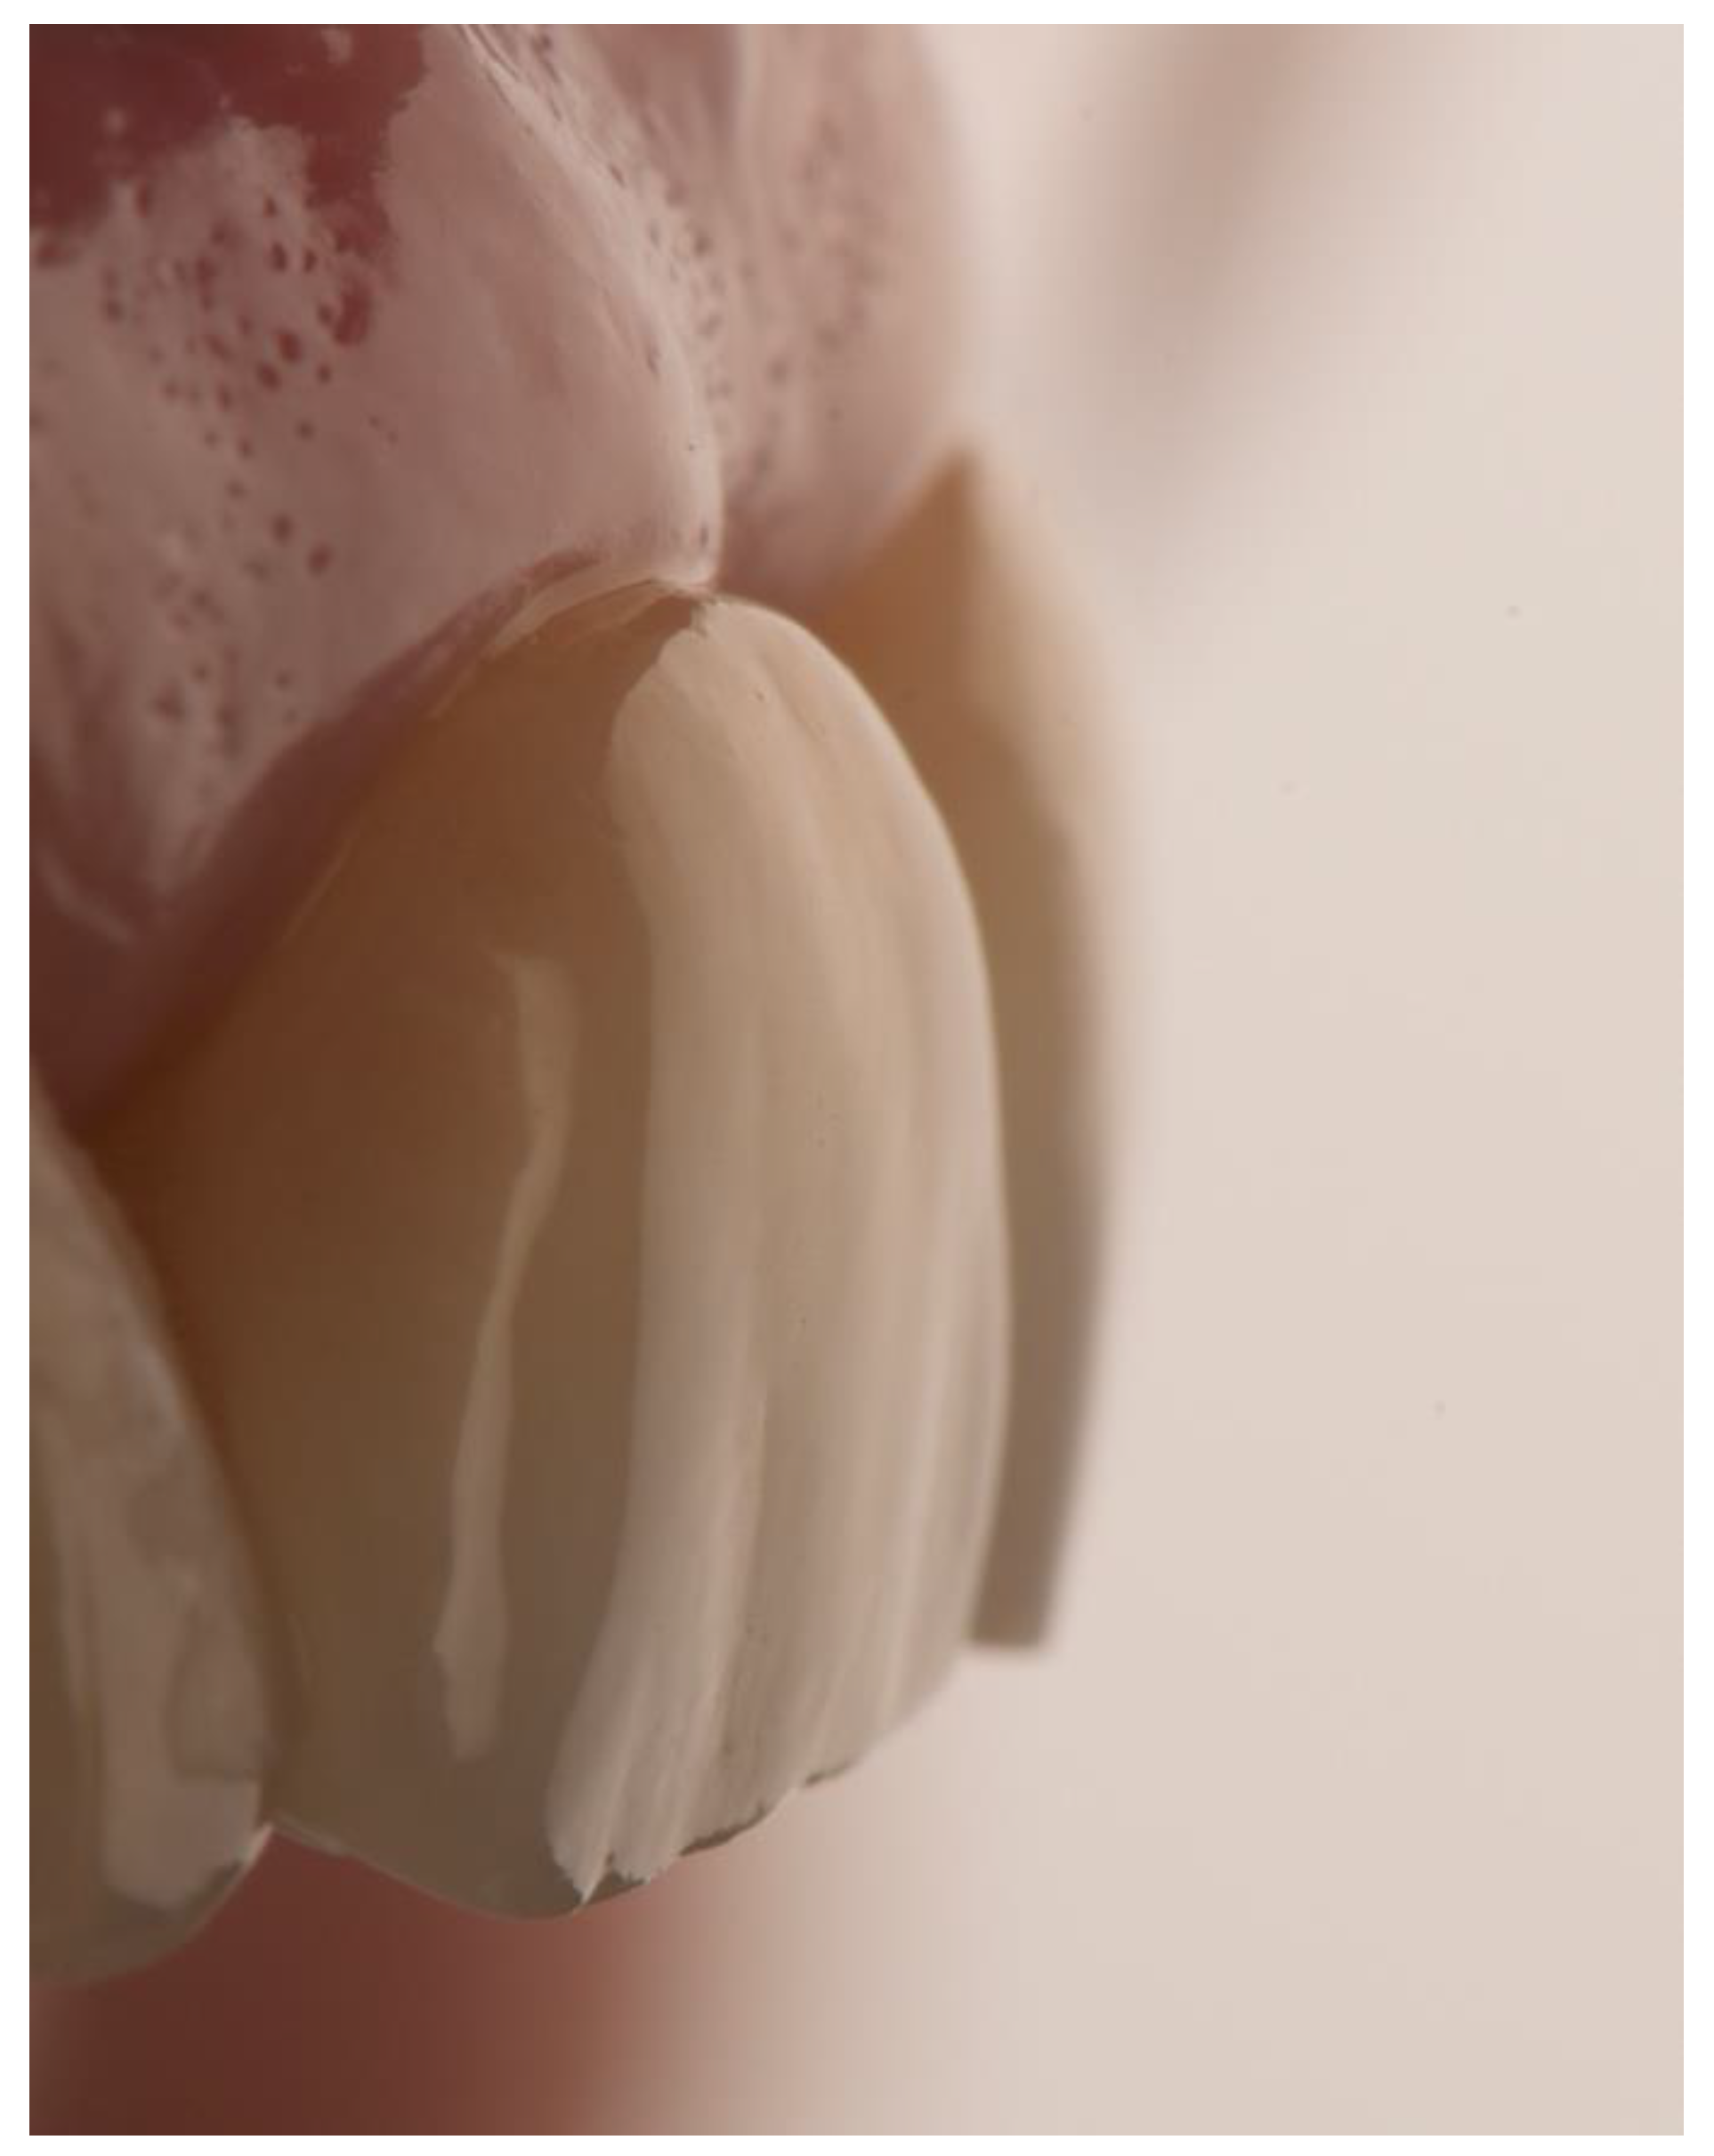

Single Crown Restorations Supported by One-Piece Zirconia Dental Implants: Case Series with a Mean Follow-Up of 58 Months

2. Materials and Methods

3. Results